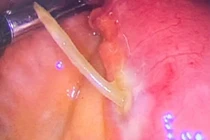

| Di vật được xác định là kẽm thường được làm hàng rào găm vào xuyên thủng phổi phải người bệnh. Ảnh: BVCC |